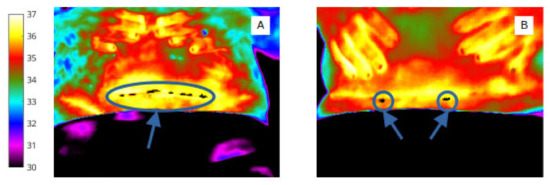

To identify pixel clusters of low temperature, shown qualitatively by the (rainbow) colour palette on the thermal image (Figure 4), automated minima regions were selected using MATLAB (by choosing continuous regions within the ROIs that are 0.5 degrees or more cooler than the surrounding areas) to produce pixel masks within the image bounding box (abdomen and wound).

Figure 4.

‘Object’ labels identify extent and site of abdominal skin ‘cold regions’ (A) and wound ‘cold spot’ clusters, (B) (shown in white for clarity in this image).